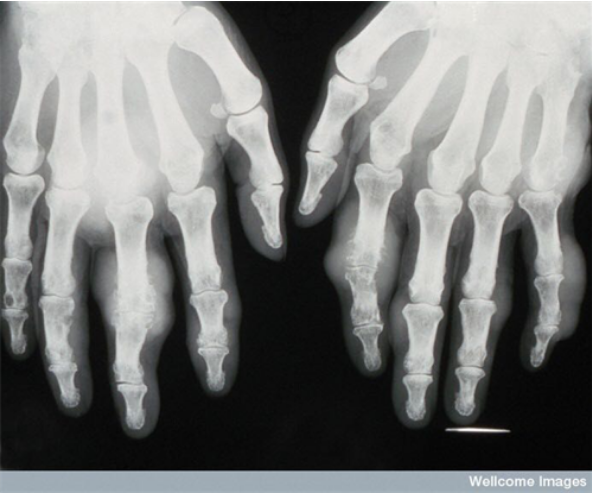

引起痛风的主要原因是体内细胞代谢形成尿酸,当体内的尿酸积聚到一定程度时,肾脏无法正常排出,当血液中尿酸浓度高于一定含量的时候(男性420umol/l,女性350umol/l),身体内的尿酸无法正常溶解,在人体关节处形成尿酸结晶,从而造成痛风患者发病关节处的极大痛苦,随着近年来现代人生活质量的不断提高,高尿酸血症/痛风已成为严重影响我国人民身体健康和生活质量的一大社会健康隐患。